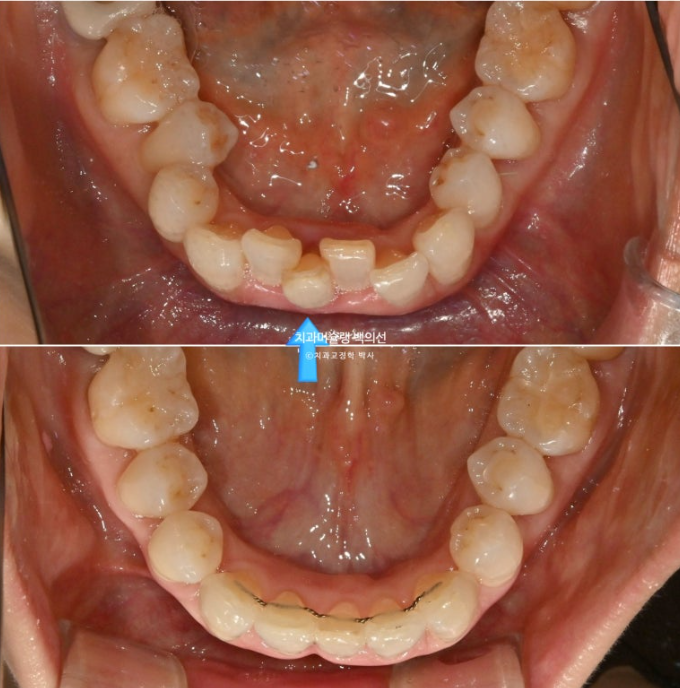

아래 앞니를 하나 빼어 그 공간으로 치아를 가지런히 하고 솟아내려온 위 앞니를 원위치 시키는 교정을 하기로 했습니다.

24.09~25.09

파란 화살표 치아가 치주염이 심해 발치한 치아입니다.

1년간의 교정치료 기간 동안 잇몸뼈는 잘 유지가 되었고 치근평행도는 양호합니다.

개인적으로 안 보이는 부분까지 완벽을 기하기 위해서 치근평행도에 집착하는 편입니다만 아래 앞니 뿌리가 완벽히 평행하지 못한 부분이 조금 아쉽습니다.

파란화살표가 발치한 치아 자리이고 이미 심한 치주염으로 골손실이 심해 인접치아 뿌리가 해당 부위로 충분히 이동해주지 못하기 때문입니다.

뼈가 튼튼해야 그쪽으로 치아이동이 잘 됩니다. 반대로 뼈가 없는 부위로 치아가 이동하진 못합니다.